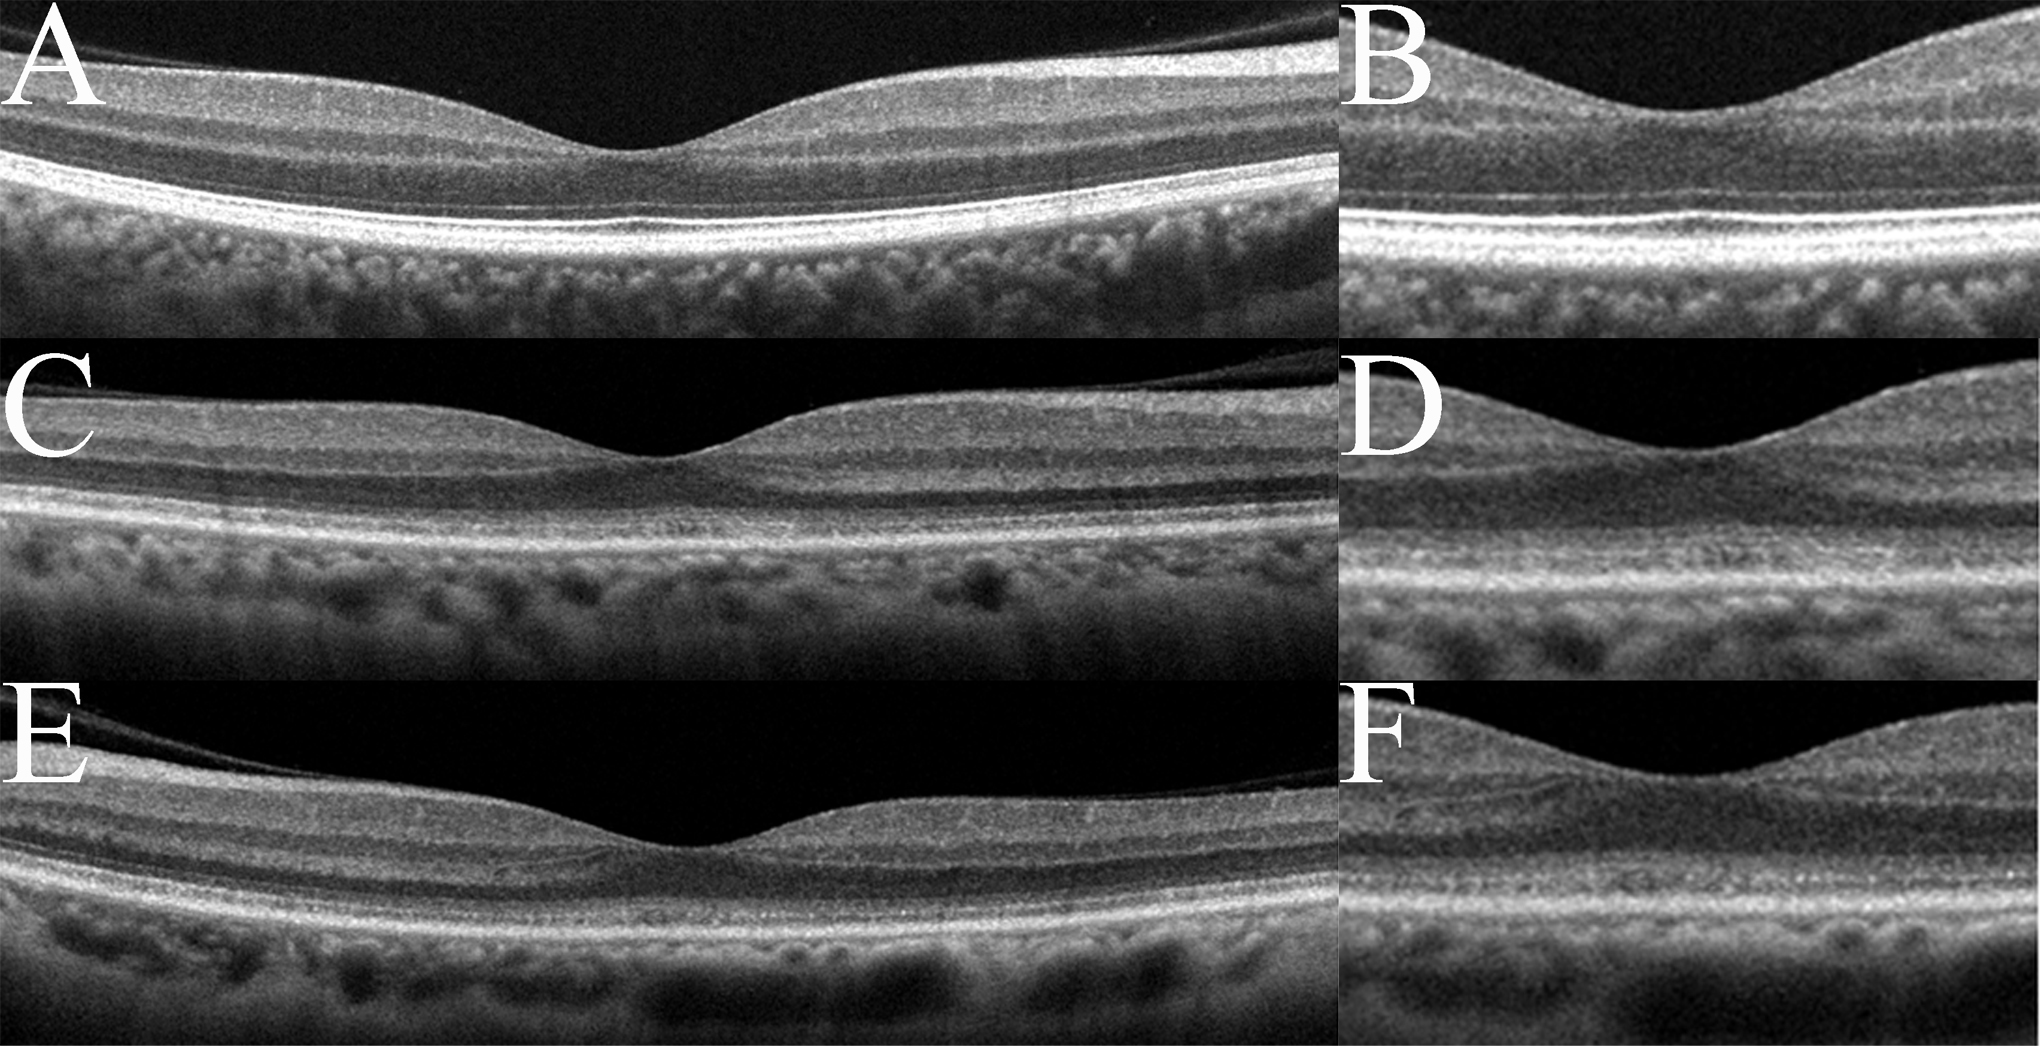

Figure 3. Spectral-domain optical

coherence tomography (SD-OCT) findings of the eyes in normal

controls (A, B) and in this case (C-F).

Images from right eyes (C, D) and left eyes (E,

F) are shown. Images at lower magnification (A, C,

E) and higher magnification (B, D, F)

are shown. The SD-OCT findings for the eyes in this case show

obvious blurring of the IS/OS junction and the COST line. The

COST line disappeared in the peripheral macula area in this

case.